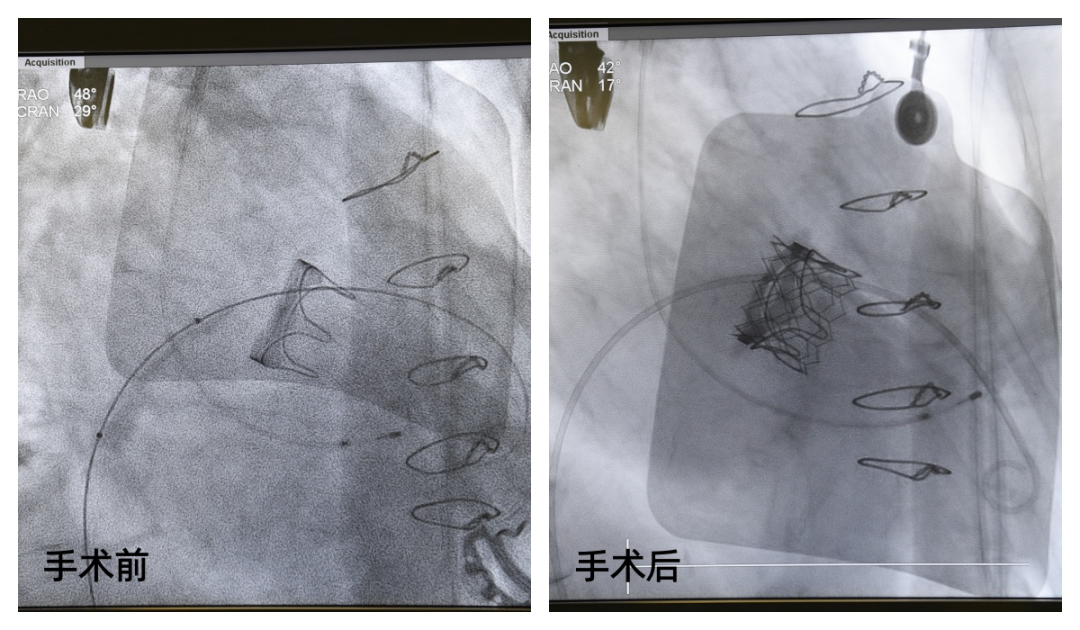

11月26日,国家心血管病中心华中分中心主任、阜外华中心血管病医院院长袁义强,结构性心脏病一病区主任刘煜昊等专家,成功实施经股静脉入路二尖瓣球扩瓣瓣中瓣置入术。

该术式在不开胸、心脏不停跳的情况下进行,仅用微创的方式就修复了患者重度受损的心脏瓣膜,挽救了83岁高龄危重患者的生命。

“成功!返流基本消失!”食道超声实时监测传来振奋人心的消息:二尖瓣返流从重度降至基本正常,跨瓣压差完全达标。手术全程出血量不足5毫升,潘女士的心脏始终保持自主跳动。